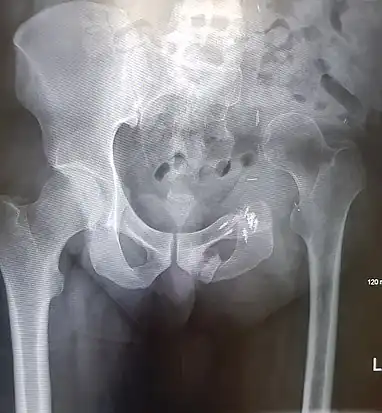

An x-ray of a limb-sparing hemipelvectomy on the left side of a male pelvis taken one month after surgery.

An x-ray of the same pelvis taken eighteen months after surgery highlighting the femur migration to its final resting place.